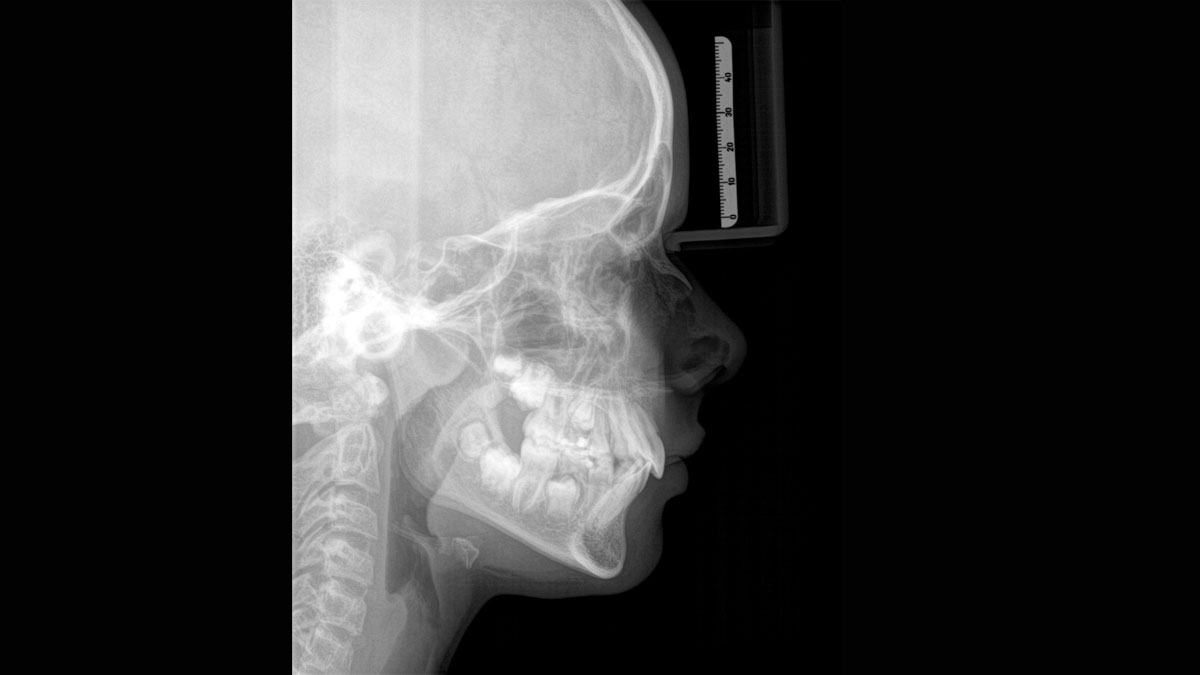

For exceptional panoramic images with high sharpness. You can choose an optional right or left cephalometric arm, which can be retrofitted at any time

The Direct Conversion Sensor (DCS) has revolutionized the standard of panoramic imaging. X-rays are converted directly into electrical signals. Thus, there is no signal loss due to light conversion, as is the case with conventional systems. The result: images with a high level of sharpness and contrast – even at an extremely low radiation dose. For accurate diagnostic information to support targeted treatment.

The image below shows a panoramic X-ray without and with DCS technology. Using the arrow, drag the control across the image to see the difference the direct conversion sensor makes to the image quality and diagnostic possibilities.

The right focus is crucial for excellent panoramic radiographs. With the autofocus function you will automatically receive an image with the best possible sharpness in focus. Dentsply Sirona Imaging devices take several thousand individual images in one cycle and automatically identify the areas where the jaw is optimally positioned. Without any additional manual steps, these images are then displayed in a final sharp image.